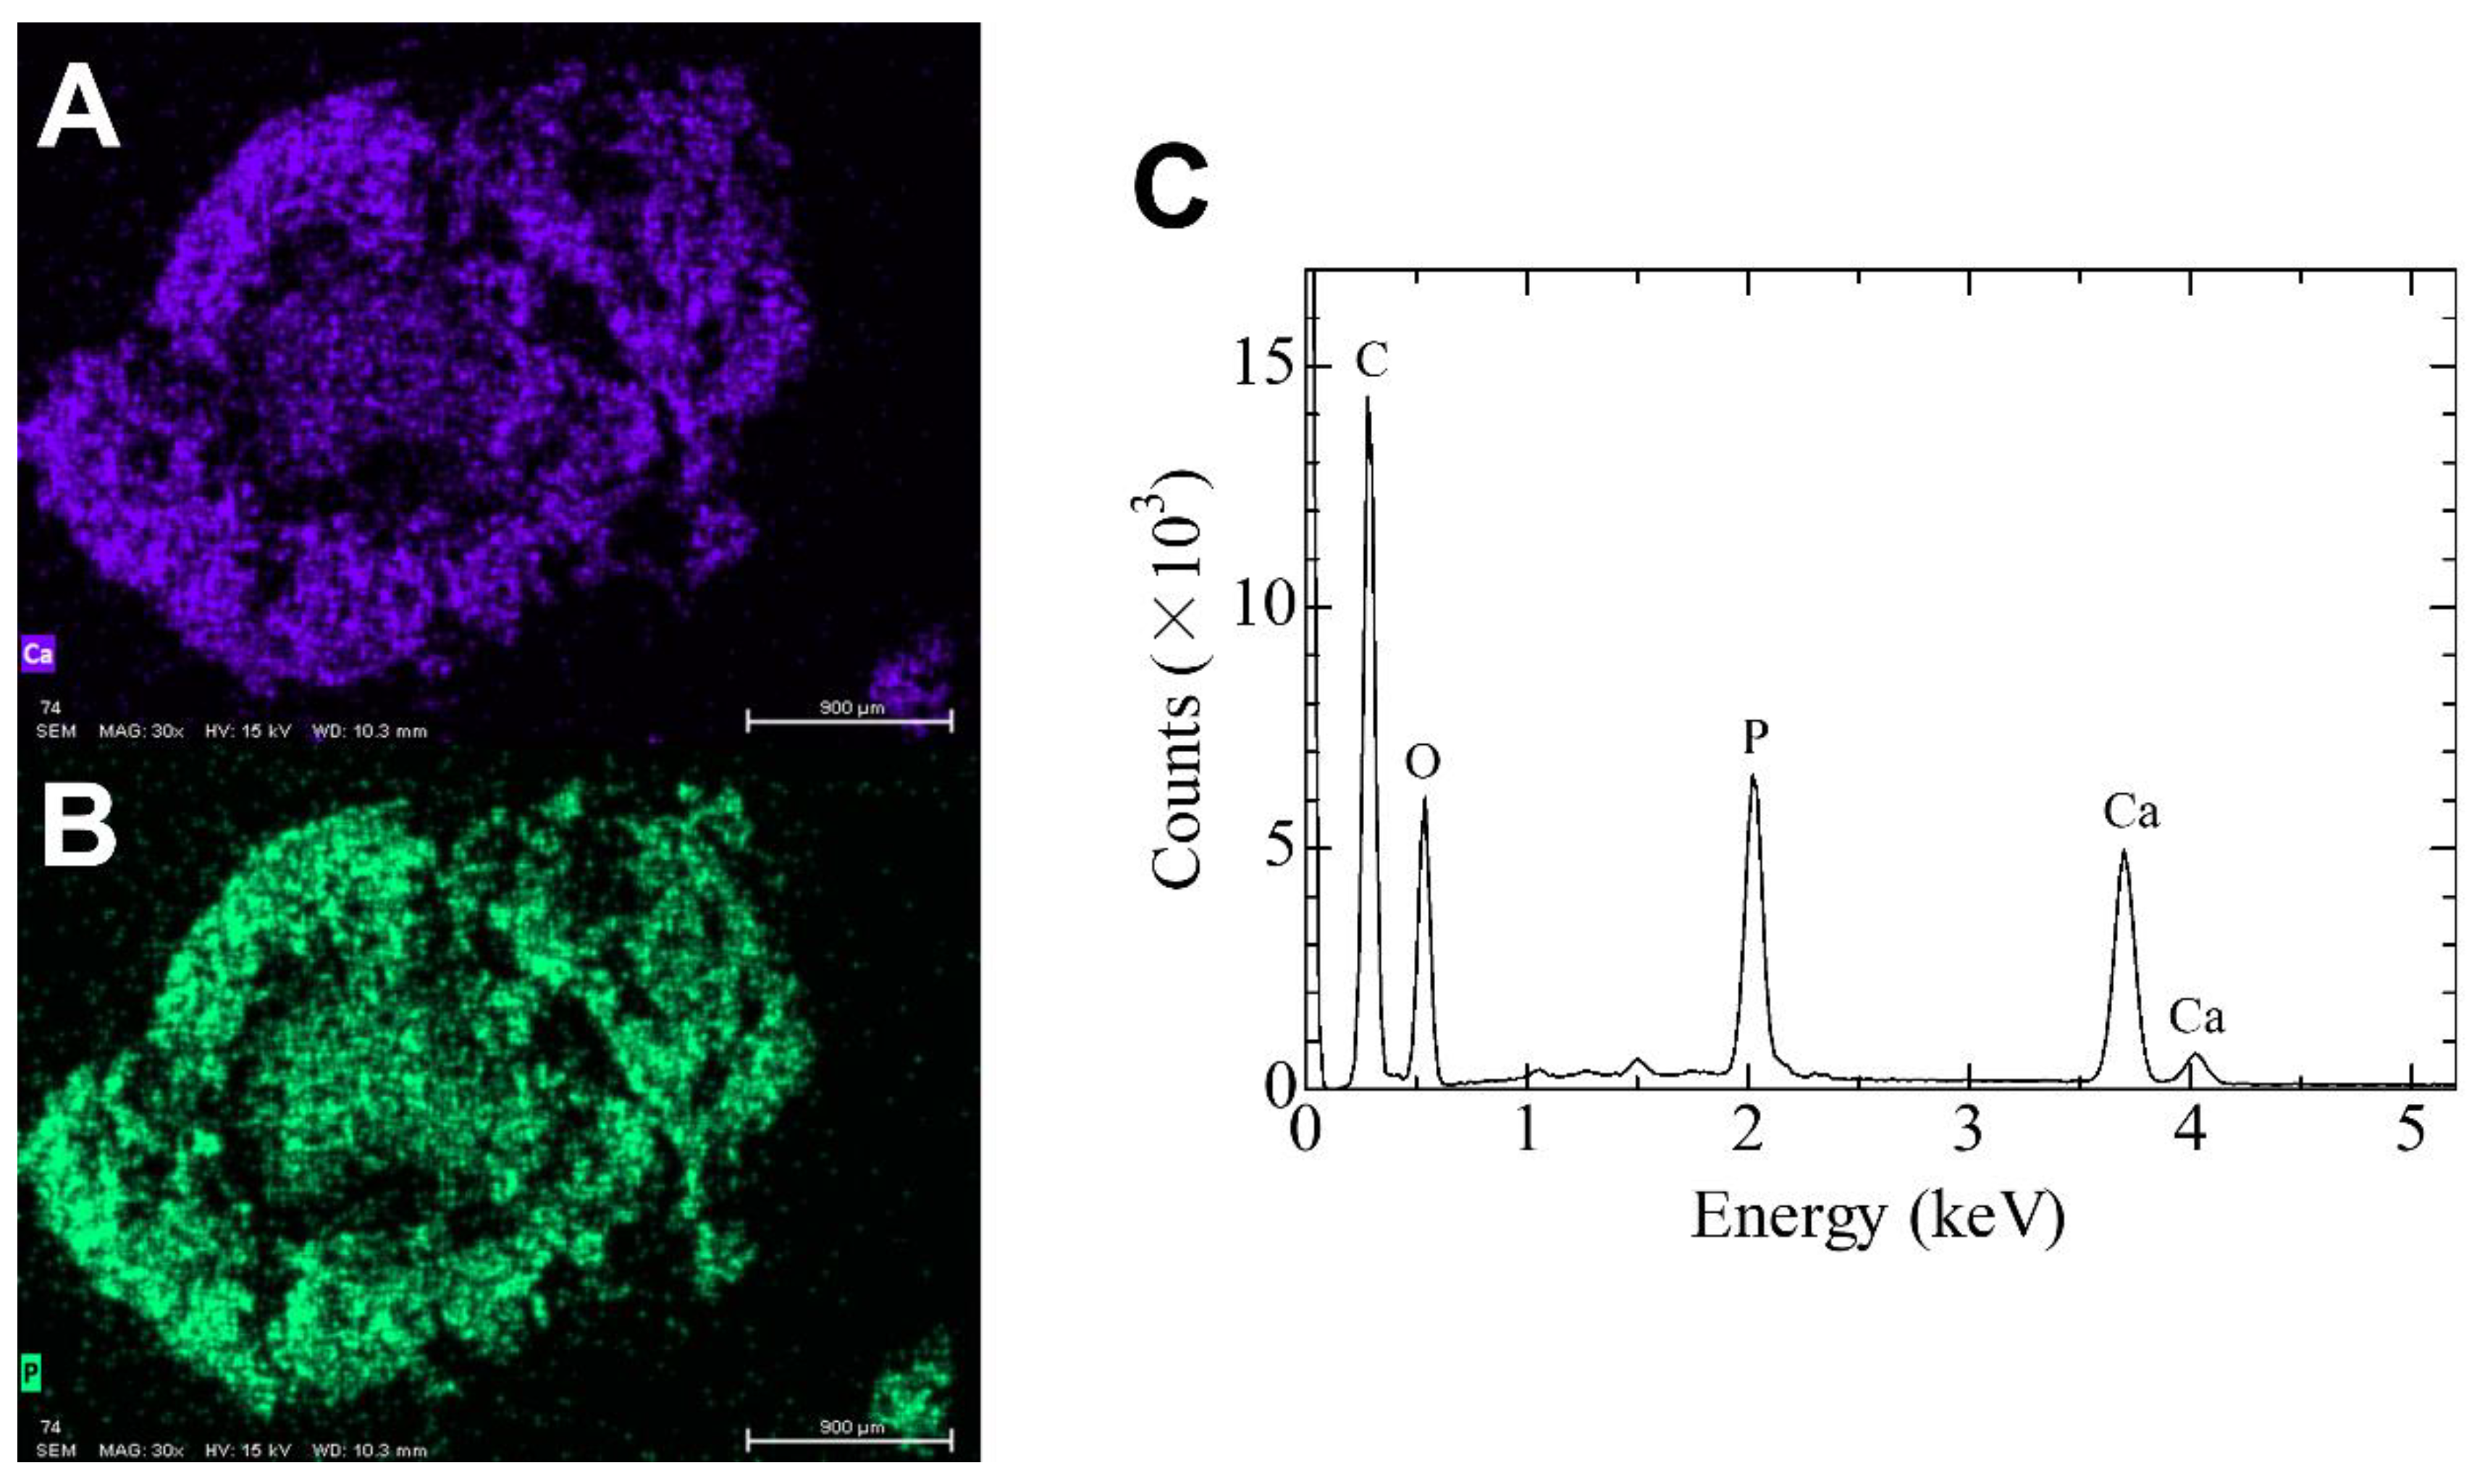

2.3. Elemental Analysis Using SEM/EDS